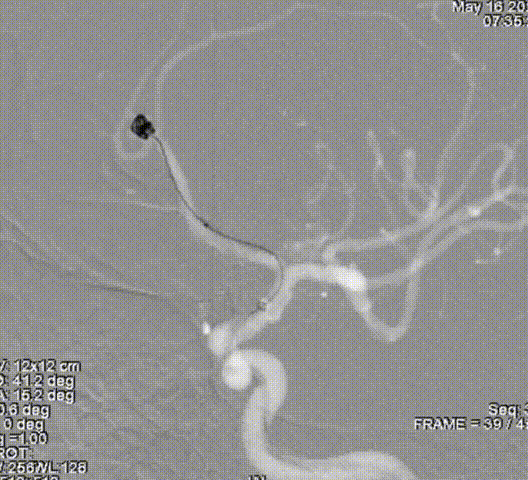

术后即刻影像

术者体会

Experience

左侧大脑中动脉分叉部动脉瘤呈分叶状,有子瘤,破裂风险大,累及大脑中动脉上下干,且动脉瘤形态不规则,需分区填塞。填塞使用的Jasper®SS弹簧圈圈体柔软,在瘤内钻缝能力强,能够很好地达到填塞效果,柔软性能强,基本不踢管,电解脱快速顺利,增加了手术的安全性及成功率。